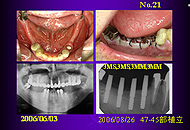

1.欠損歯数と植立本数 1)欠損歯数と同本数の植立: 35症例 76本

2)欠損歯数より多い本数の植立: 4症例 13本

3)欠損歯数より少ない本数の植立:2症例 8本

欠損歯数と植立本数では「同本数」が多く、これが原則であると思う。 「多い本数」は右下765や左下567の3本欠損に3mmAQBを4本植立した場合や、近遠心径があって頬舌径が狭いため直径5mmAQBの植立ができないような右下6部に4MMと3MMを植立した場合が含まれる。 「少ない本数」は上顎前歯小臼歯部の5本欠損で、切歯管部位の植立を避けたため、3mmAQBを4本植立した場合である。